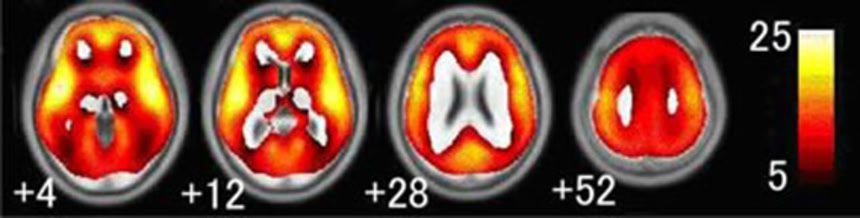

大脳を輪切りにした標本(年齢別)

脳のいちばん表面にある大脳皮質に覆われ、灰色に見える部分が灰白質。その内側に白く見える部分(白質)があり、ここは神経細胞同士をつなぐ神経繊維の束が走っている場所。さらにその内側には「脳室」といって脳脊髄液という水がたまっている場所がある。(ソース)

この画像を大きなサイズで見るちなみに灰白質は神経細胞の集まりで、年齢と共に割合が小さくなり、萎縮してくる。この為、年をとるにしたがって認知など、脳が情報を処理する能力が衰えるそうだ。ということは、灰白質が大きいと、老後ボケる心配が減るってことでいいのかな?